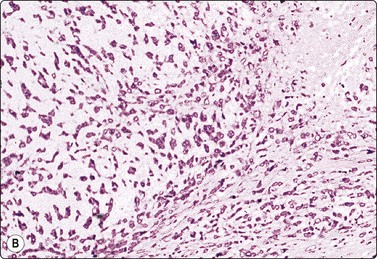

image image

Fig. 7.31 Malignant phyllodes tumor

(A) Mainly dispersed spindle cells showing moderate nuclear atypia, no epithelial cells. Invasive growth demonstrated in tissue sections; multiple recurrences (MGG, IP); (B) Another case showing numerous spindle cells with more marked atypia and a sheet of bland epithelium (Pap, HP).